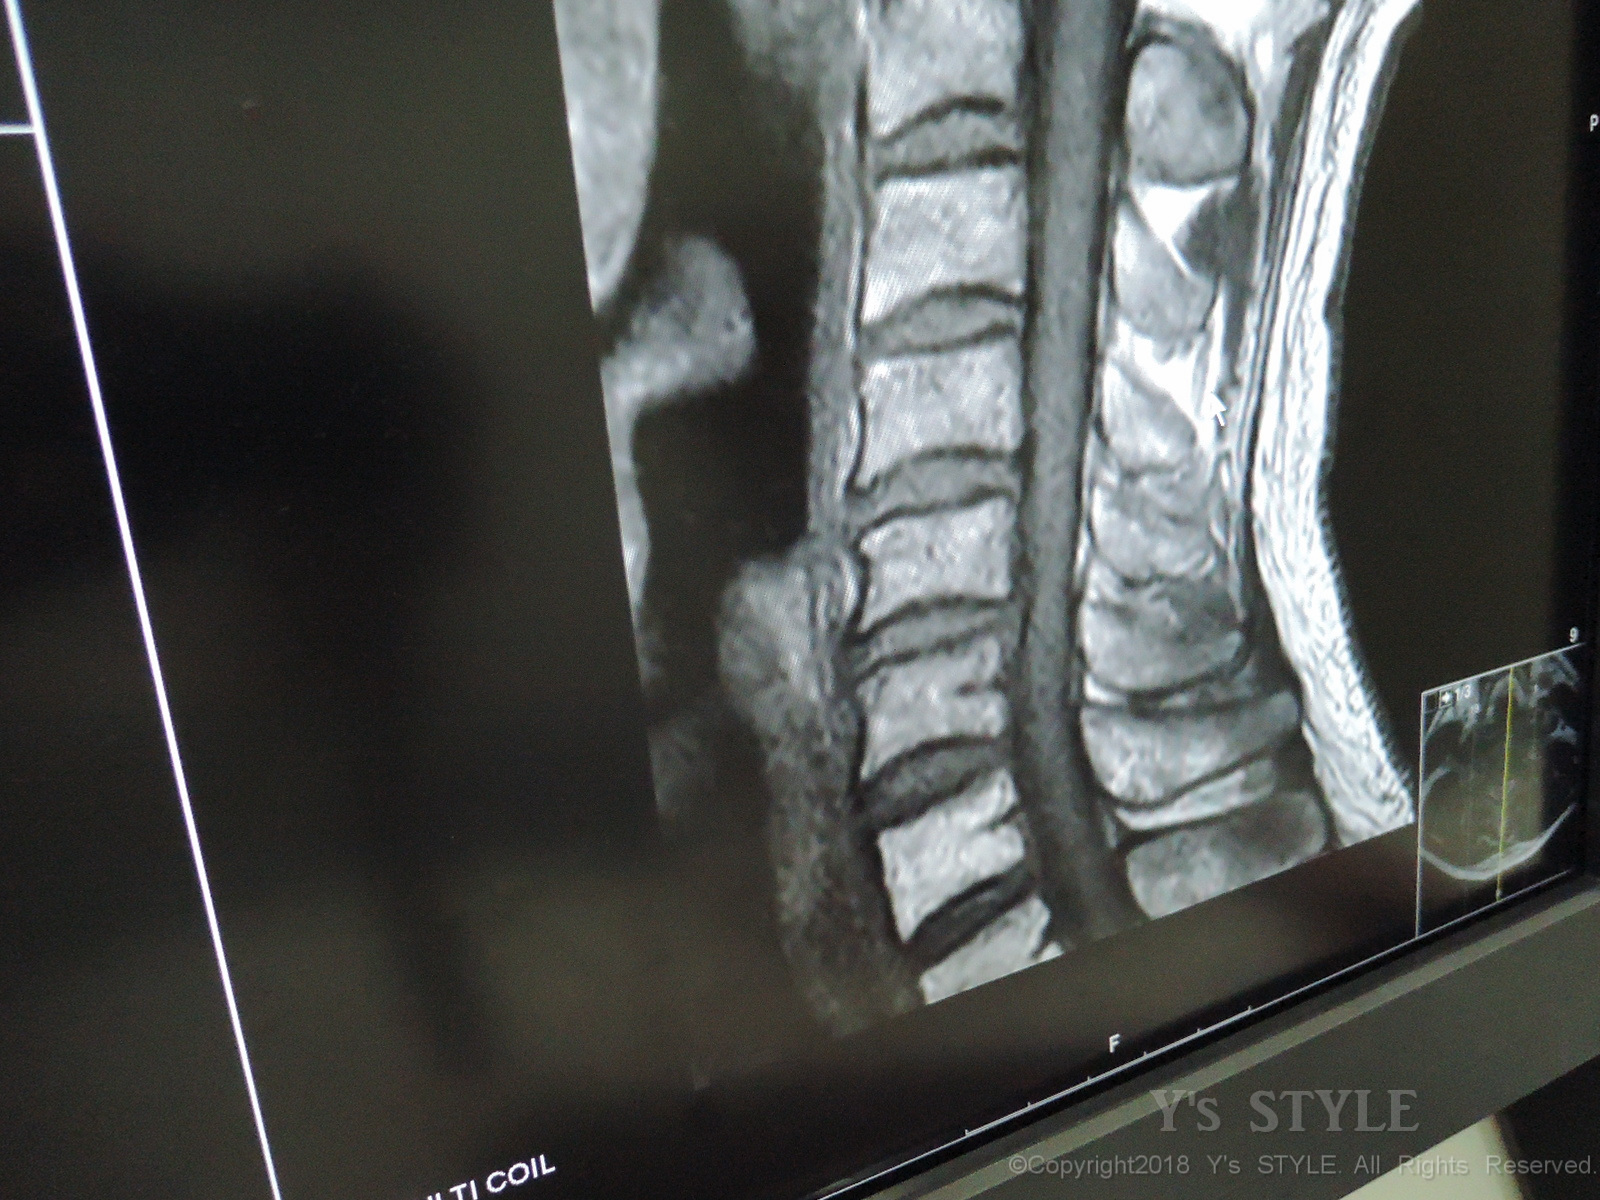

画像診断(MRI)って結構よく映るのね・・・(;´Д`)

横から見るとこんな感じで結構行っちゃってます(;・∀・)